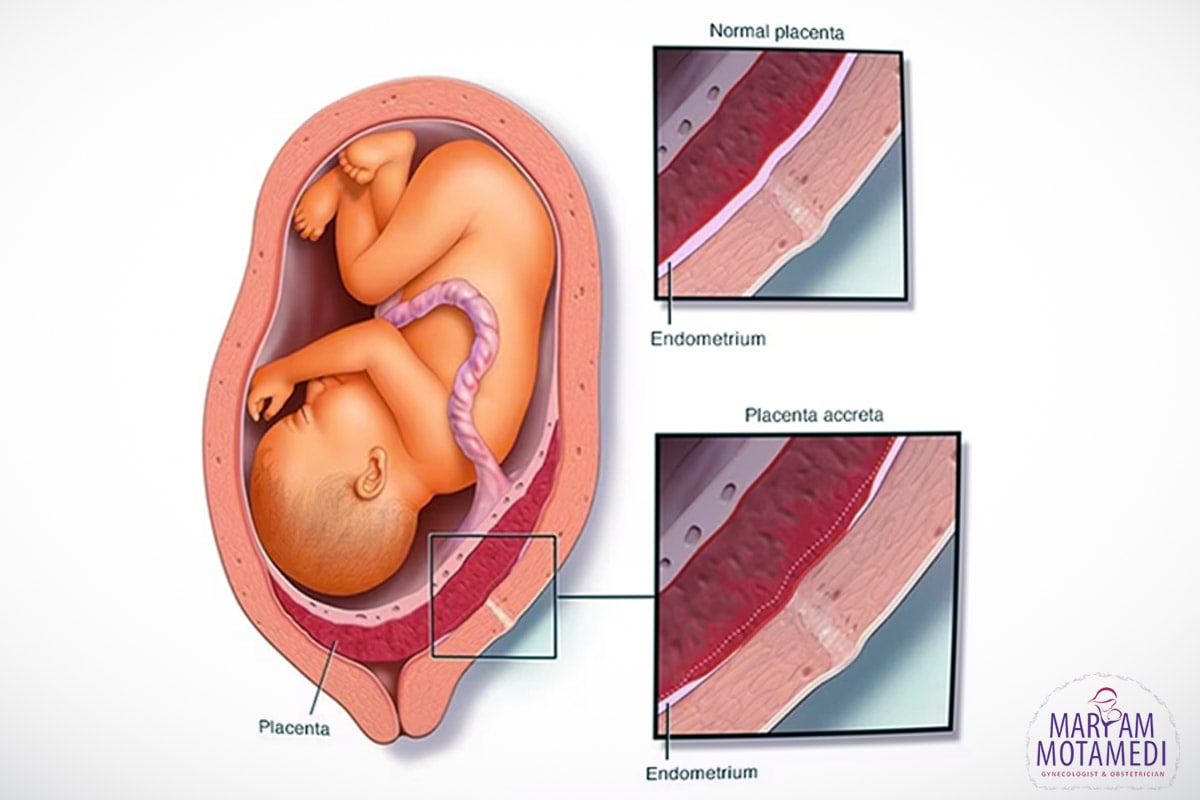

چسبندگیِ جفت چیست؟

مفهوم چسبندگی جفت به معنای تعامل و ارتباط نزدیک و هماهنگی بین جنین و رحم مادر می باشد. این ارتباط اساسی برای رشد و توسعه ی سالم جنین و حفظ بارداری است.

وقتی یک تخمک تخمدانی تلقیح شده و به رحم متصل می شود، فرآیندی به نام “پیوند” اتفاق می افتد. در این فرآیند، جنین به رحم متصل می شود و مادر، با استفاده از پوشش رحمی و ارتباطات مولکولی، از جنین محافظت می کند و تأمین مواد غذایی و اکسیژن به آن را فراهم می سازد.

چسبندگی جفت در بارداری اهمیت بسیاری دارد، زیرا نقص در این ارتباط می تواند منجر به مشکلاتی مانند بارداری خرج از رحم، ناتوانی در بارداری ، خطر ایجاد ترشحات و یا بروز عفونت های رحمی شود. بنابراین، این چسبندگی جفت برای حفظ بارداری سالم و توسعه ی نرمال جنین بسیار حیاتی است.

به طور کل باید گفت که اغلب پس از تولد جنین، جفت از دیواره ی رحم جدا می شود. اما در صورت بروز عارضه ی چسبندگیِ جفت، بخشی از جفت یا تمامی آن به دیواره ی رحم چسبیده باقی می ماند. این امر منجر به بروز خونریزی شدید پس از زایمان می شود که می تواند خطرناک باشد.